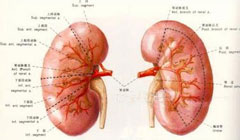

急性肾衰竭(ARF)

疾病介绍:急性肾衰竭(ARF)是指肾小球滤过功能在数小时至数周内迅速降低而引起的以水、电解质和酸碱平衡失调以及氮质代谢产物蓄积为主要特征的一组临床综合症,…【详细】